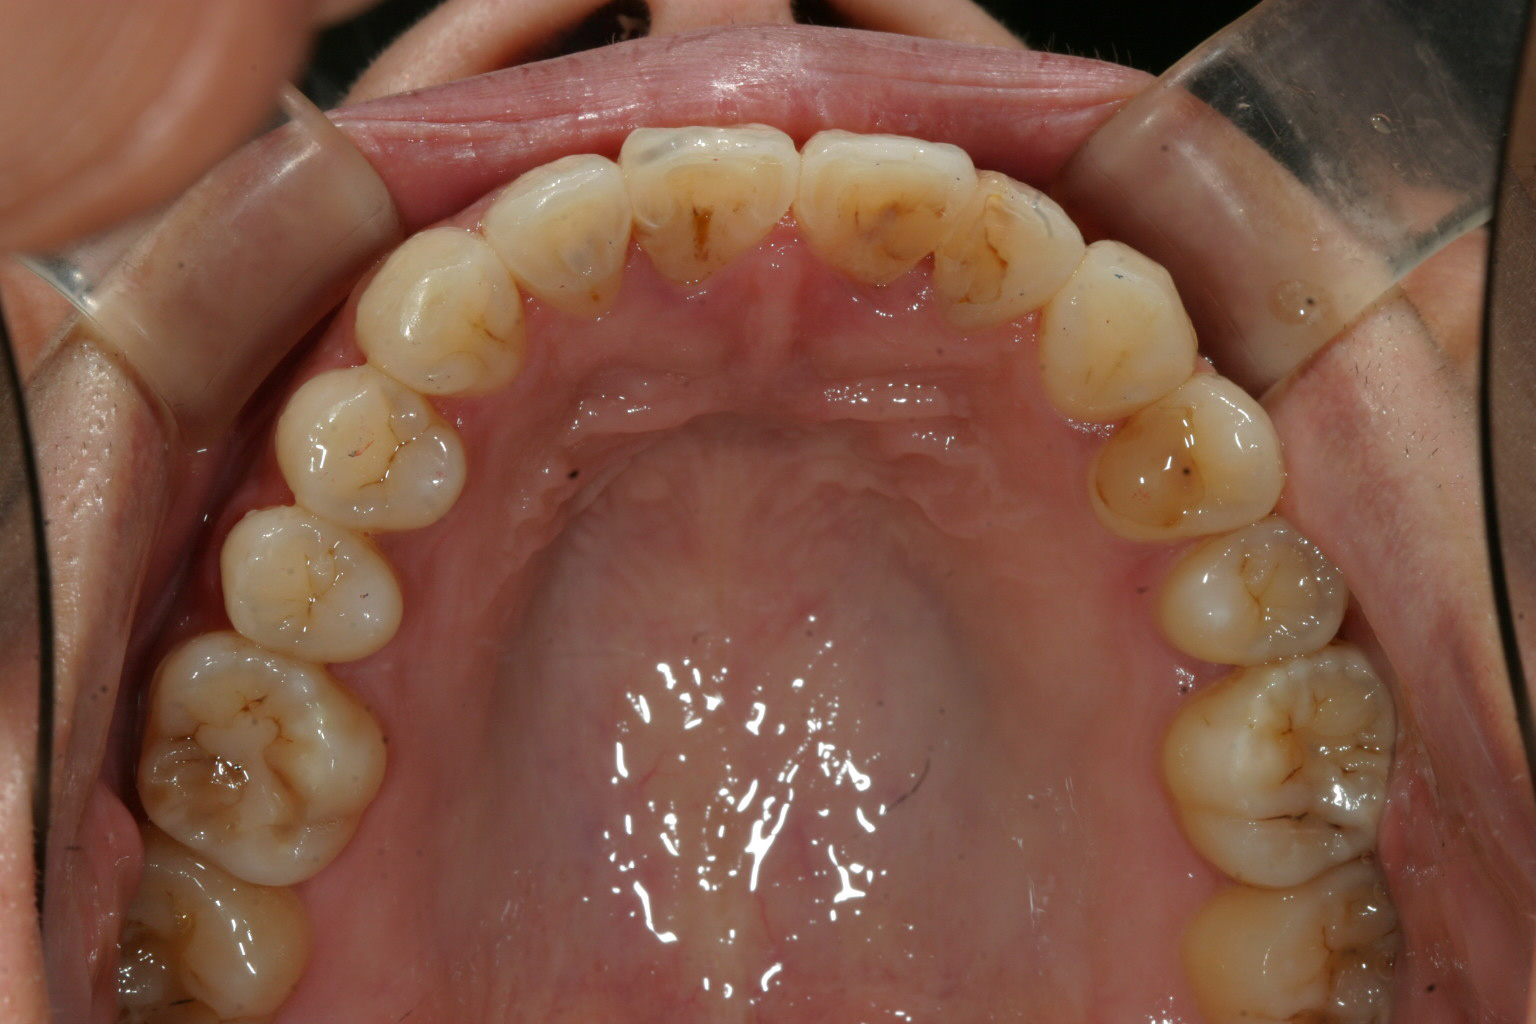

綺麗に改善してますね~ 患者様がかなり頑張ってチューイ咬んで頑張ってくれました。

下顎もいい感じです。

前突感も最高です。